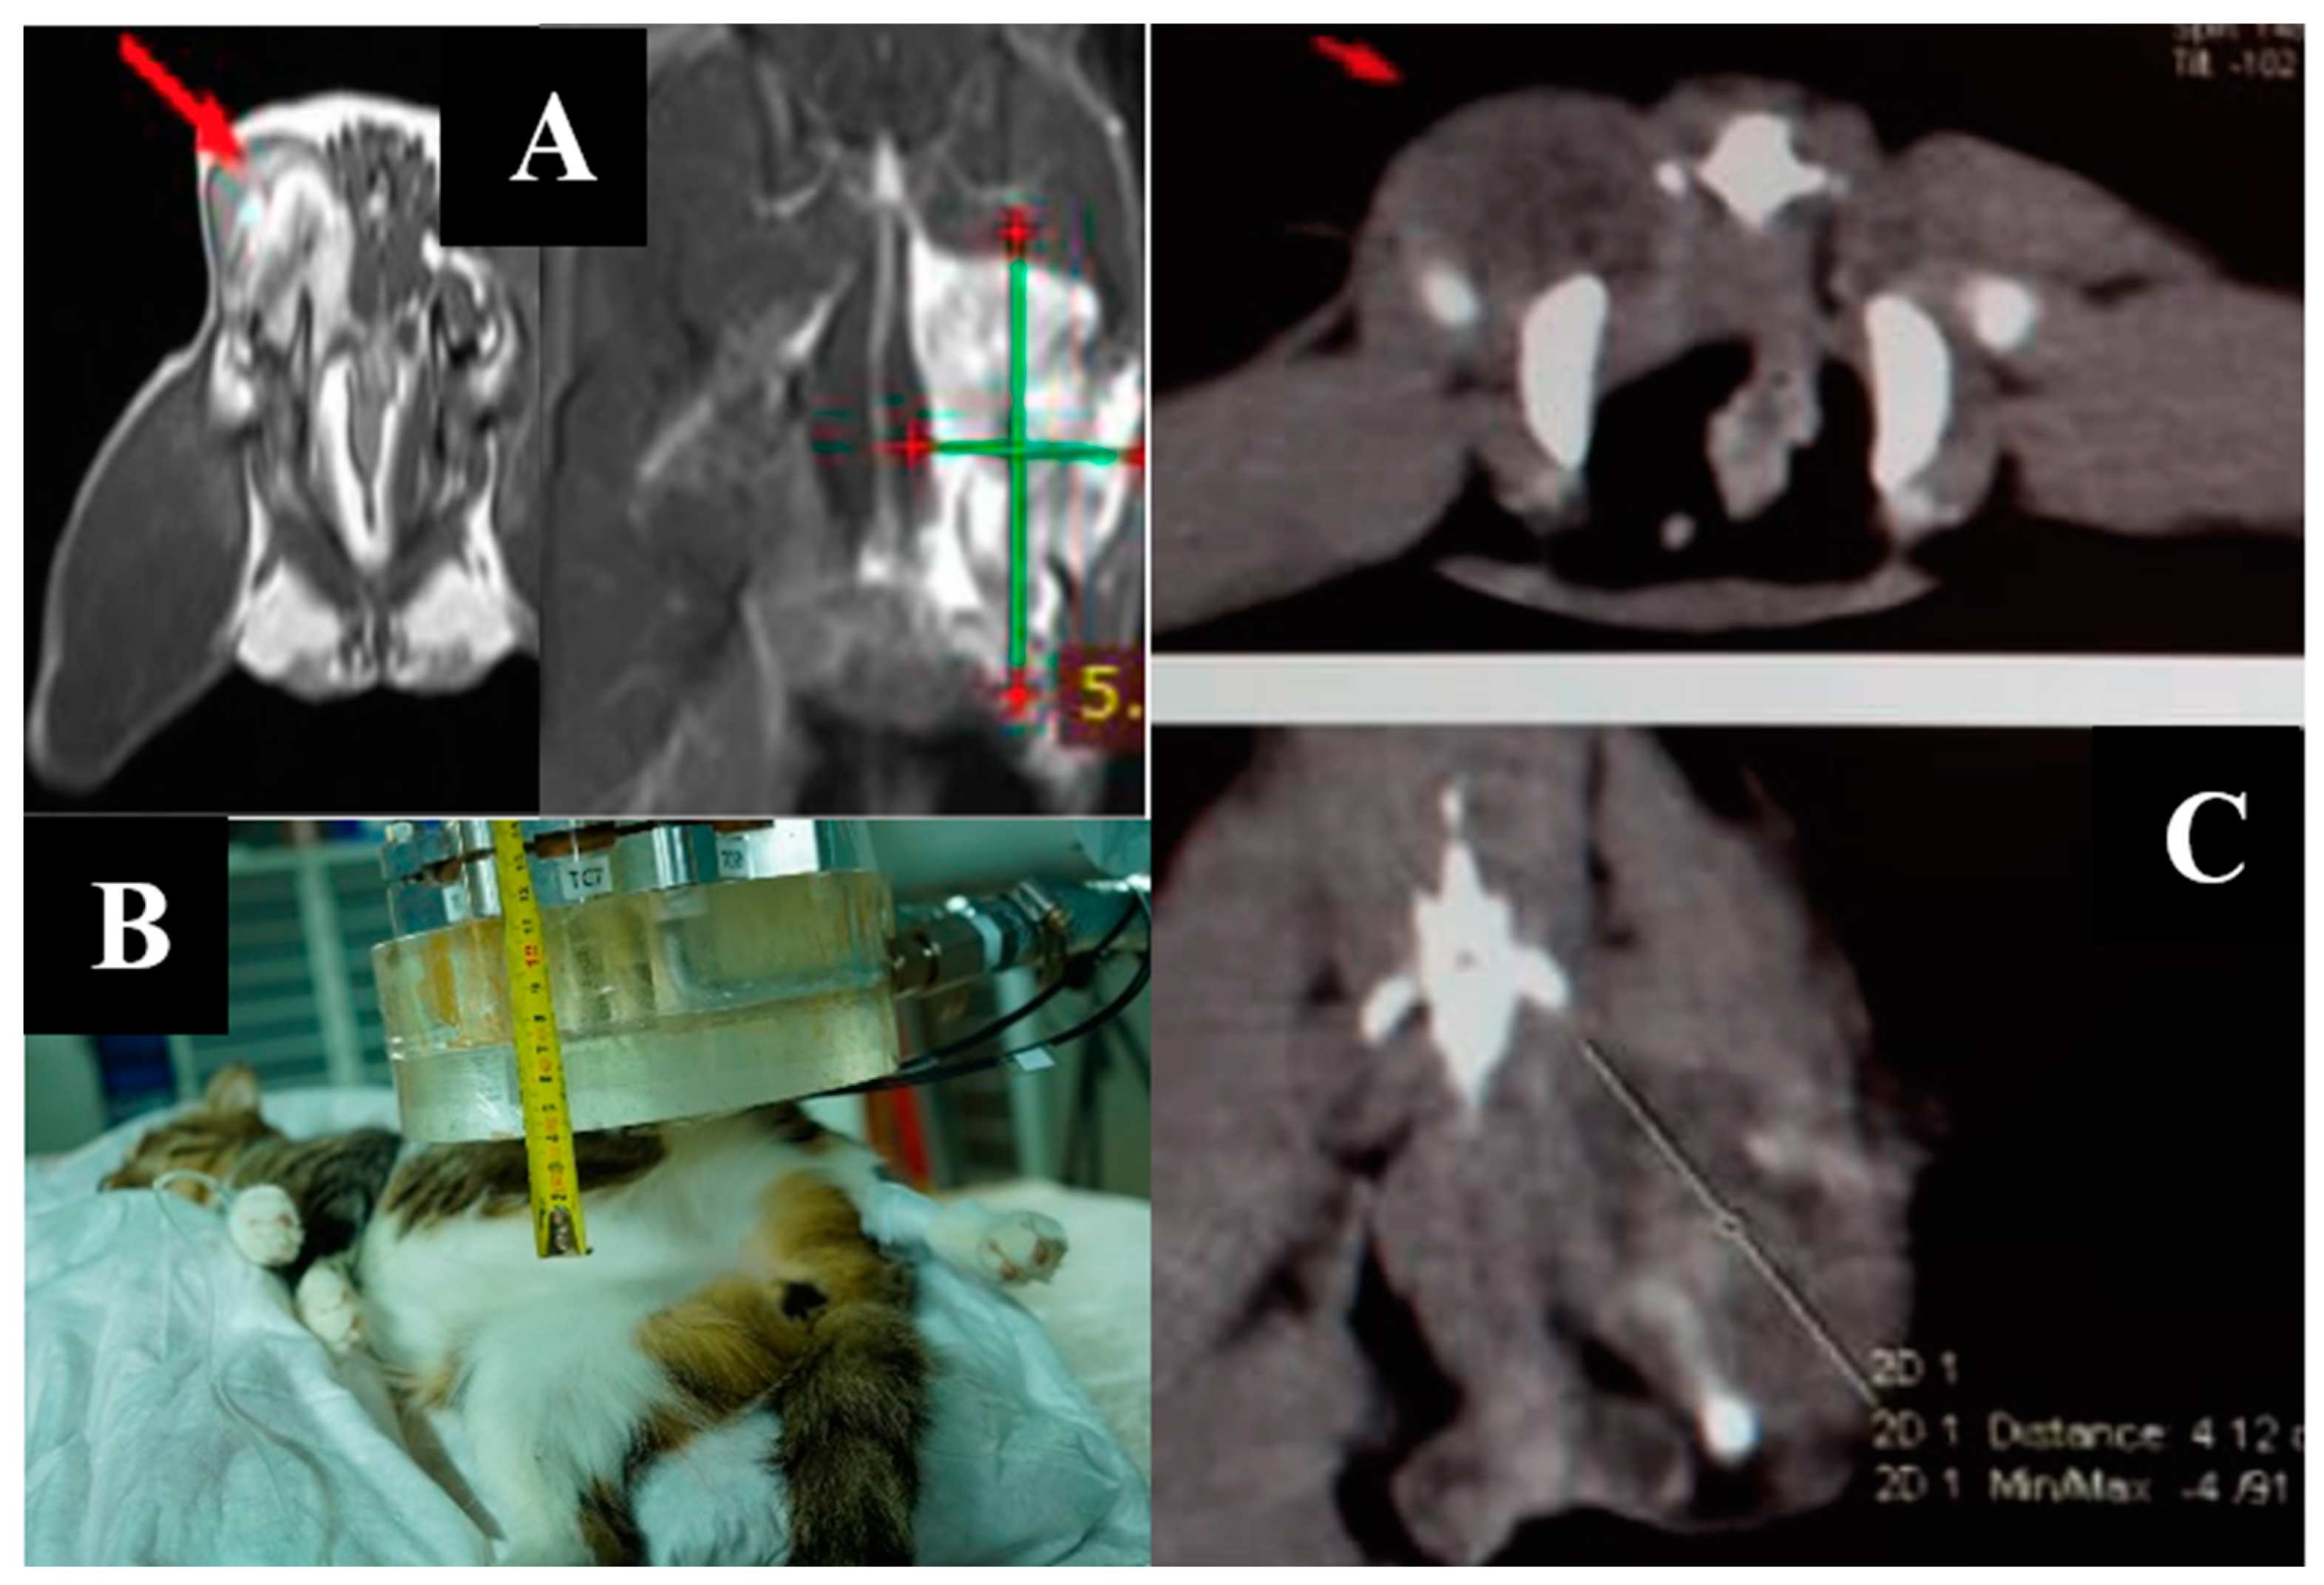

3.5. Case 5

3.6. Case 6

3.7. Case 7

3.8. Case 8

3.9. Case 9